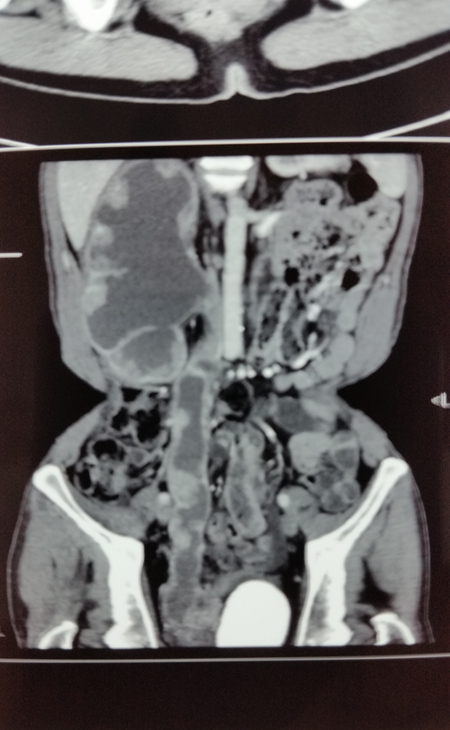

CT增强扫描示右肾、右输尿管多发性肿瘤

日前,泌尿外科王金根主任医师为一位罕见的肾、输尿管、膀胱多发性肿瘤患者成功实施了切除手术,一次性完整切除右肾、右输尿管和全膀胱,术后没有并发症,病理切片证实为腺癌,各切缘均未见癌细胞(表明切除彻底),患者顺利康复出院。患者是一位54岁男性,因反复肉眼血尿2年余,右侧腰痛2月余入院。入院后经相关检查很快确诊了病情:右侧肾盂肾盏、右输尿管全长和膀胱内均生长了大量肿瘤,同时合并感染发烧,膀胱内还有一个巨大结石,此外还存在严重贫血和营养不良,全身水肿。手术切除是患者目前唯一的治疗选择。由于长期梗阻,右侧肾盂肾盏和输尿管重度扩张,加上近期合并感染,肾脏周围广泛粘连,手术分离过程中肾脏及输尿管壁极易破损,一旦破损将会导致肿瘤扩散,严重影响疗效。因此手术难度极大,风险很高,对手术医生的技术要求非常高。王金根博士组织全科专家反复讨论制定治疗方案,并亲自带领治疗组进行充分细致的术前准备。2014年6月9日,由王博士主刀,在全麻下为患者施行了手术。手术中发现患者右肾体积巨大,与腰背部肌肉、肝脏、结肠和下腔静脉等重要器官广泛紧密粘连,手术难度比术前估计的还要大。为了解除患者的病痛,挽救患者的生命,王金根博士、贾灵华硕士和包佑根医生等组成的手术小组迎难而上,历经八个小时的艰苦努力,终于将患者的右肾、输尿管和膀胱完整切除,邻近器官完好无损。